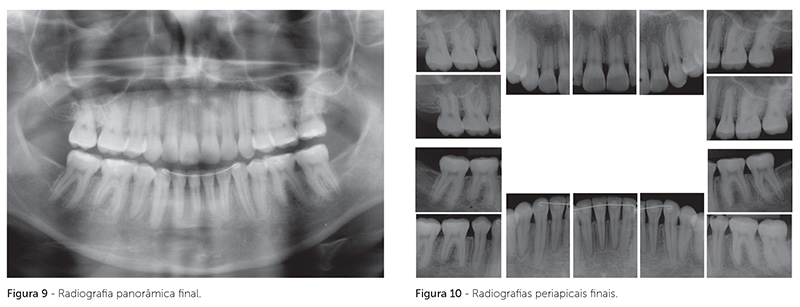

Houve manutenção da posição vertical tanto da maxila quanto da mandíbula, com leve redução do ângulo SNA, o que levou à redução do ângulo ANB (Tab. 1). Foi obtida relação de chave de oclusão nos molares e caninos, em ambos os lados, com fechamento da mordida aberta posterior, correção da sobressaliência e contração das arcadas superior e inferior (Fig. 7, 8).

Foi observada diminuição de 10mm e 11mm, respectivamente, na distância intermolares superiores e inferiores, e diminuição de 3mm na distância intercaninos superiores e inferiores, em ambas as arcadas. Observou-se leve aumento do ângulo nasolabial, devido à retrusão dos dentes anteriores superiores, com pouca alteração do perfil facial, permanecendo a ausência de selamento labial passivo e a hiperatividade do músculo mentalis.

Foi obtido bom paralelismo radicular ao final do tratamento, conforme observado na radiografia panorâmica (Fig. 9). As radiografias periapicais mostraram leve aumento no remodelamento apical dos incisivos (Fig. 10).

Nas sobreposições cefalométricas, observa-se que houve extrusão do primeiro molar superior, que foi compensada pelo movimento mesial do molar inferior (Fig. 13, 14), o que contribuiu para a manutenção do ângulo do plano mandibular. A grande redução obtida nas distâncias intermolares provavelmente foi favorecida pela movimentação para mesial desses dentes, que passaram a ocupar uma região mais estreita dos ossos basais. Como contenção, utilizou-se barra lingual intercaninos, na arcada inferior, e placa removível tipo wraparound, na superior.